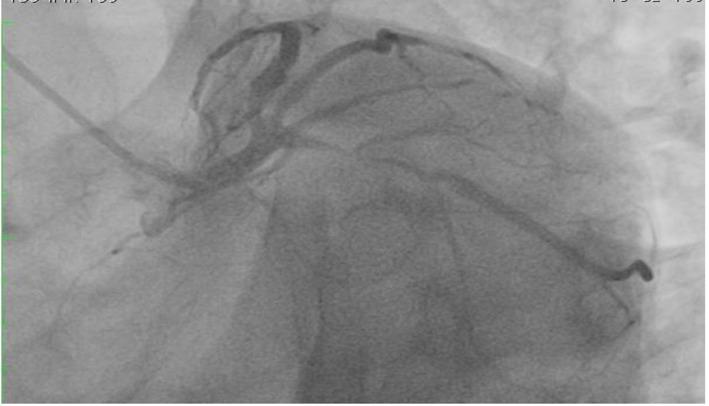

Although most of the patients presenting with ischemic heart disease have chest pains, there are other rare presenting symptoms like cardiac cephalgia. In this report, we present a case of acute coronary syndrome with an only presentation of exertional headache. It was postulated as acute presentation of coronary artery disease, due to previous history of similar presentation associated with some chest pains with previous left coronary artery stenting. We present an unusual case with cardiac cephalgia in a young patient under the age of 50 which was not reported at that age before. There are four suggested mechanisms for this cardiac presentation.

虽然大多数缺血性心脏病患者会出现胸痛,但也有其他罕见的症状,如心源性头痛。在本报告中,我们介绍了一例急性冠状动脉综合征,其唯一表现为劳力性头痛。由于既往有类似表现且伴有胸痛,曾行左冠状动脉支架置入术,故推测为冠状动脉疾病的急性表现。我们报告了一例50岁以下年轻患者的心源性头痛的罕见病例,此前该年龄段未见报道。关于这种心脏表现有四种推测机制。